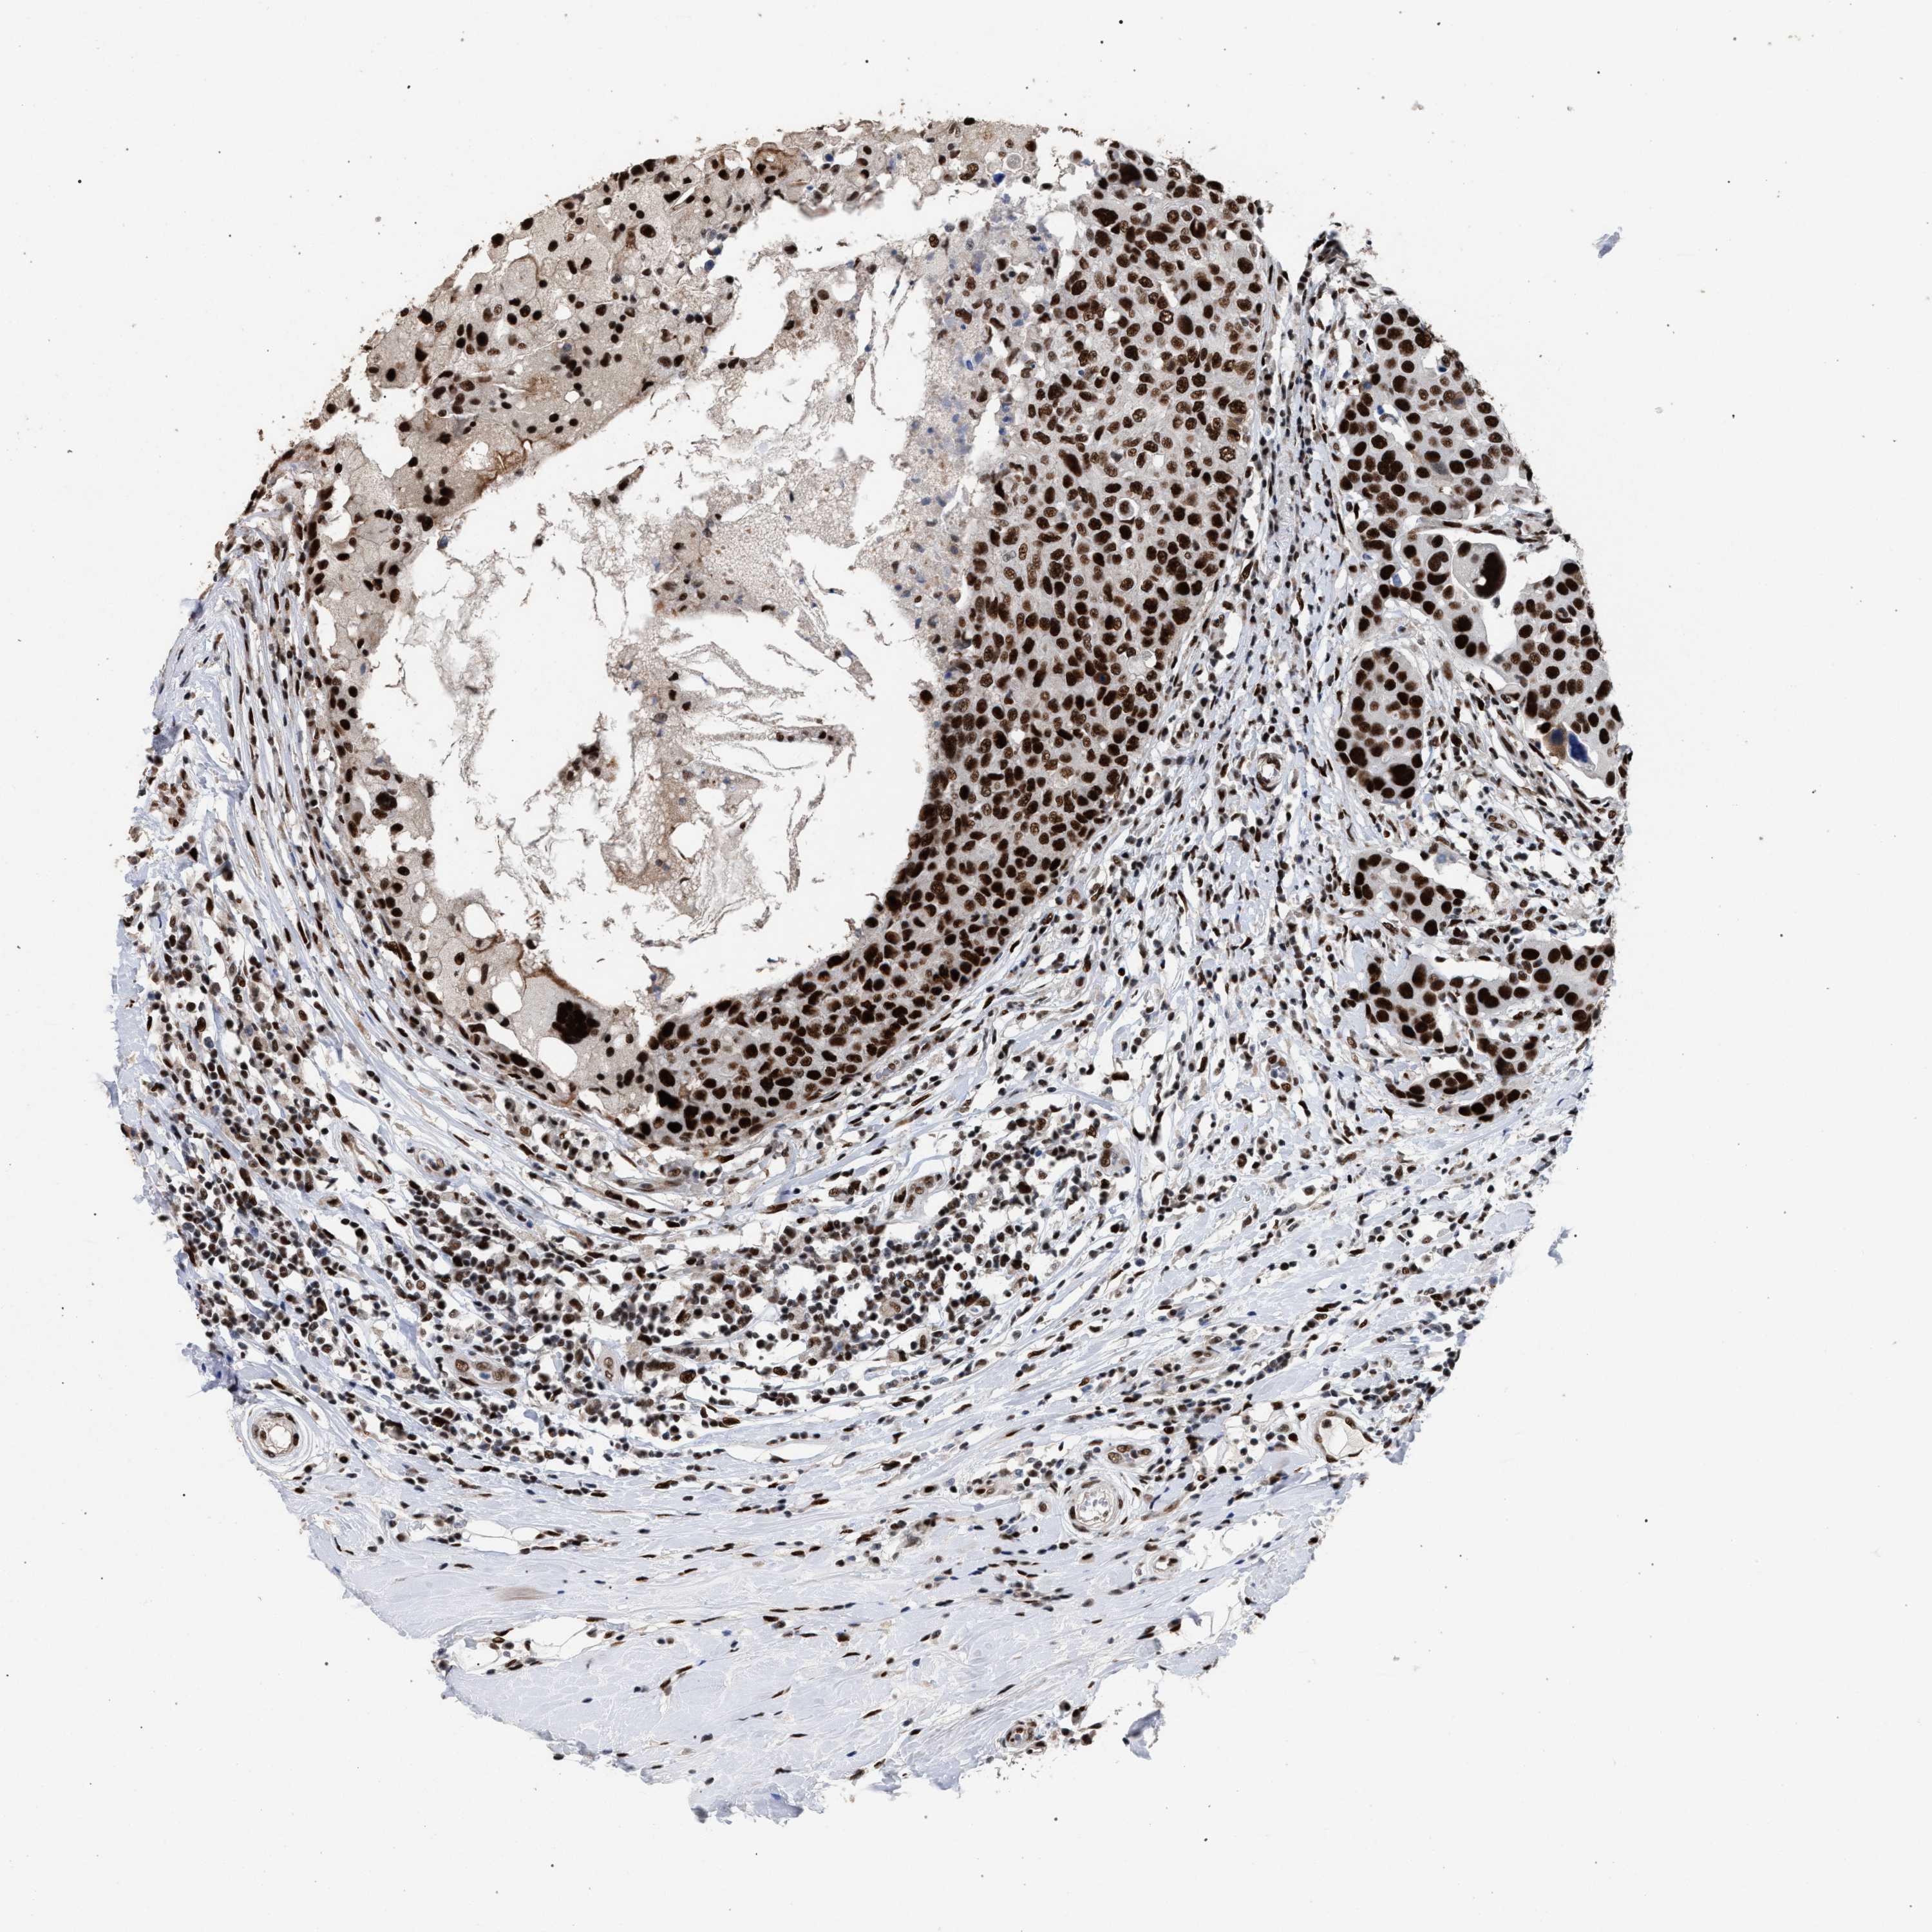

CANCER BREAST CANCER Show tissue menu

BRCA TCGA BRCA VALIDATION PROTEIN EXPRESSION

ANTIBODIES

AND

VALIDATION